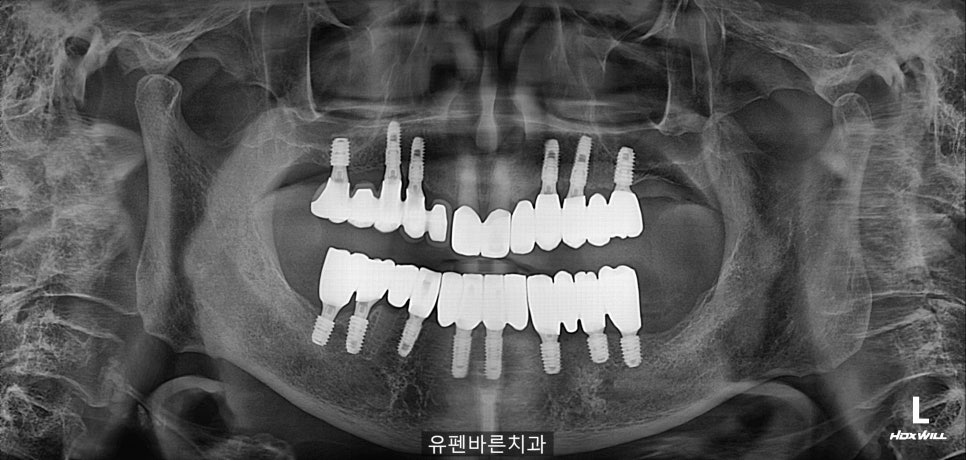

상악에 6개, 하악에 8개

총 14개의

임플란트 수술을

잘 마쳤습니다.

임플란트들이

아주 예쁘게

잘 심어진 것 같죠?

잇몸에 닿았던 앞니가..

맞물리는 치아가 생기고,

무너져 있던 교합이

바로잡아지면서

환자분께서

식사를 잘 하실 수 있게

되셨어요 .